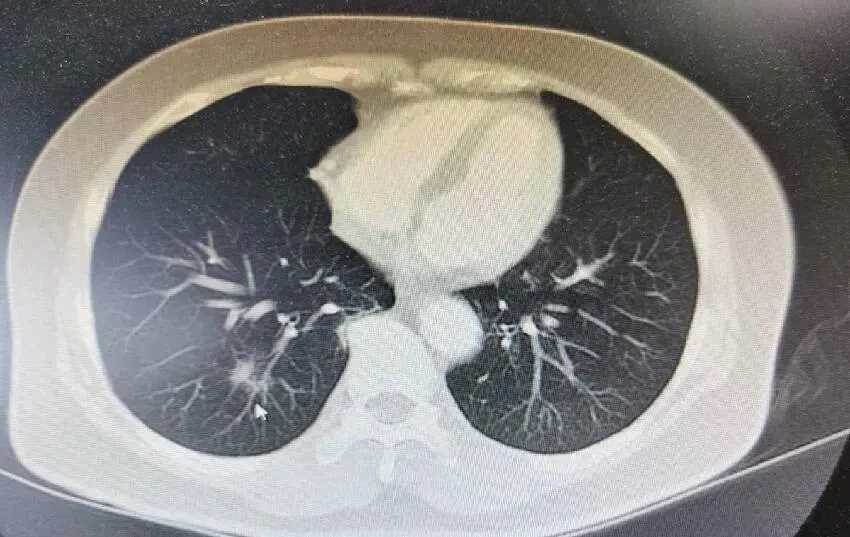

建議大家這個時候可以選擇去醫院拍一下CT照片,檢查一下肺部是否有問題,早發現早治療,以免延誤病情。